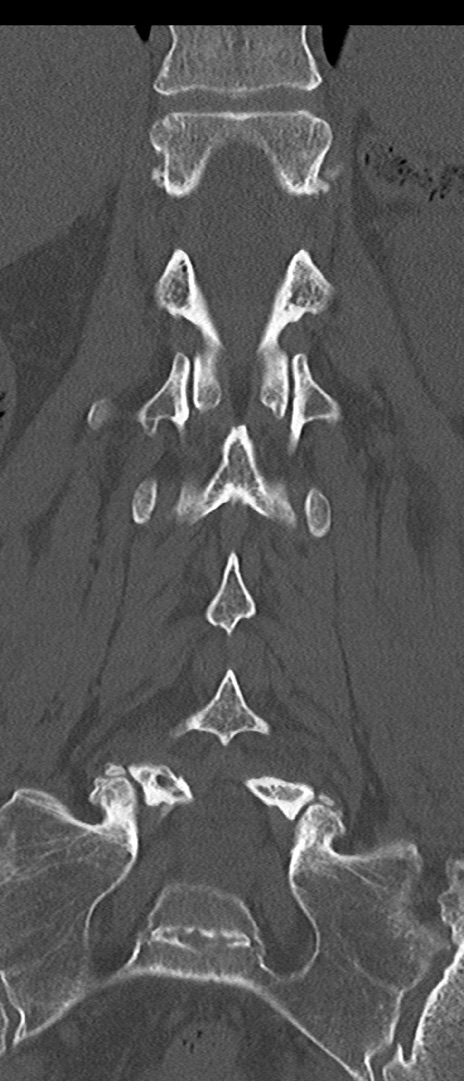

腰椎CT

矢状断像